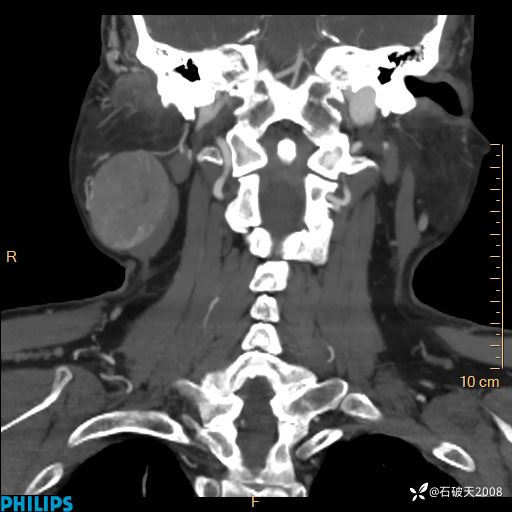

病例分享:颈部占位,一周后公布病理

男 57岁 主 诉:发现右侧颌下肿物1月余。

现病史:1月余前家属发现右侧颌下肿物。局部皮肤无红肿、热痛,无吞咽困难,无异物感,无恶心、呕吐,无头痛、头晕,无胸闷、胸痛,无发热、咳嗽、咳痰及呼吸困难。于我院行体表肿块彩超检查(2024.03.15我院)示:右侧耳下皮下软组织内低回声,未治疗。今为进一步治疗门诊以“腮腺肿瘤”为诊断收住我科,发病来患者神志清,精神可,饮食、睡眠及大小便正常,体重无明显下降。

平扫